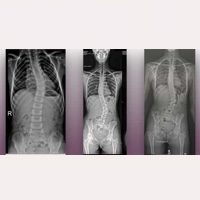

Evolució post-operatòria favorable d’una pacient pediàtrica amb Escoliosi Idiopàtica, als 4 anys de l’aplicació del Filum System® Llegir més » 09 gener, 2026